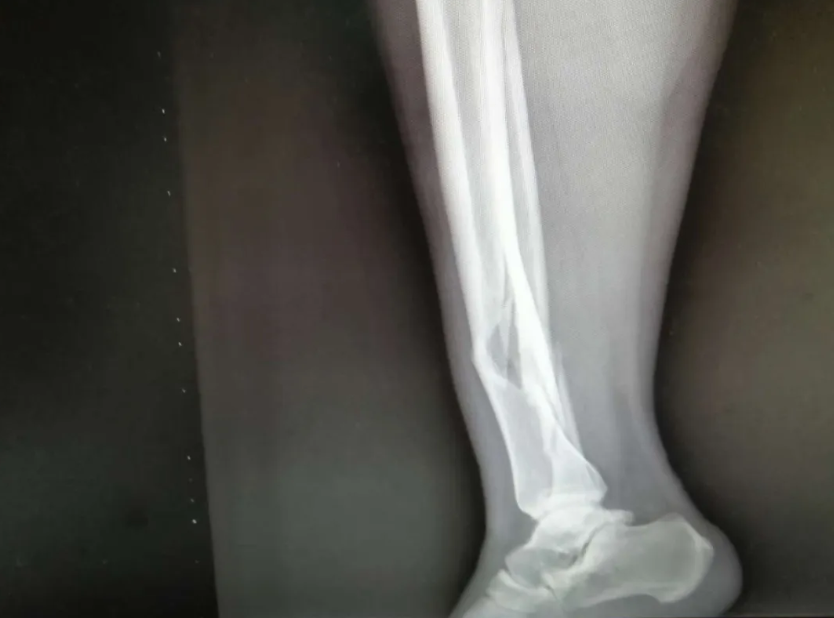

来到医院后,经过门诊检查和摄片后初步诊断为“右胫腓骨粉碎性骨折”,骨科谢业东主任详细的询问病情和经往病史后,首先予以手法牵引复位石膏外固定以减轻患者骨折错位后的疼痛,防止断裂后的骨头尖锐处磨破皮肤后造成感染,打完石膏后杨女士在护士和家属的陪同协助下回到了病房,然后护士对患者用冰敷减轻内出血和水肿,预防血栓形成。住院第二天,医生在例行查房的时候见到杨女士的患肢肿胀,石膏要比前一天紧了一点,于是给她松开后予以重新固定,让病人感到舒适,也能防止患肢因过度包扎导致血流不通畅,造成坏肢。

随后,医生根据杨女士的自身情况对她说明要等到患肢消肿后方可行手术,没消肿做手术的话会对术后伤口愈合不良,但考虑到其患肢自行消肿时间会比较长,所以建议予中药外敷以减轻肿胀和疼痛情况,杨女士表示接受治疗。中药外敷了几天后,效果明显,护士查房的时候问到患者感受,杨女士说第一天就感觉到效果了,明显没有之前那么痛了,于是在患肢消肿后就可以准备做手术了,谢业东主任给患者耐心讲解术前、术中、术后的注意事项以及术后的功能锻炼,杨女士在了解自己的治疗方案后,对手术更有信心了,在完善了术前相关检查后,手术于3月22日上午进行,行右胫腓骨开放复位内固定术,手术过程非常顺利,患者恢复良好,术后在医生护士的指导下进行康复功能锻炼,现已康复出院。